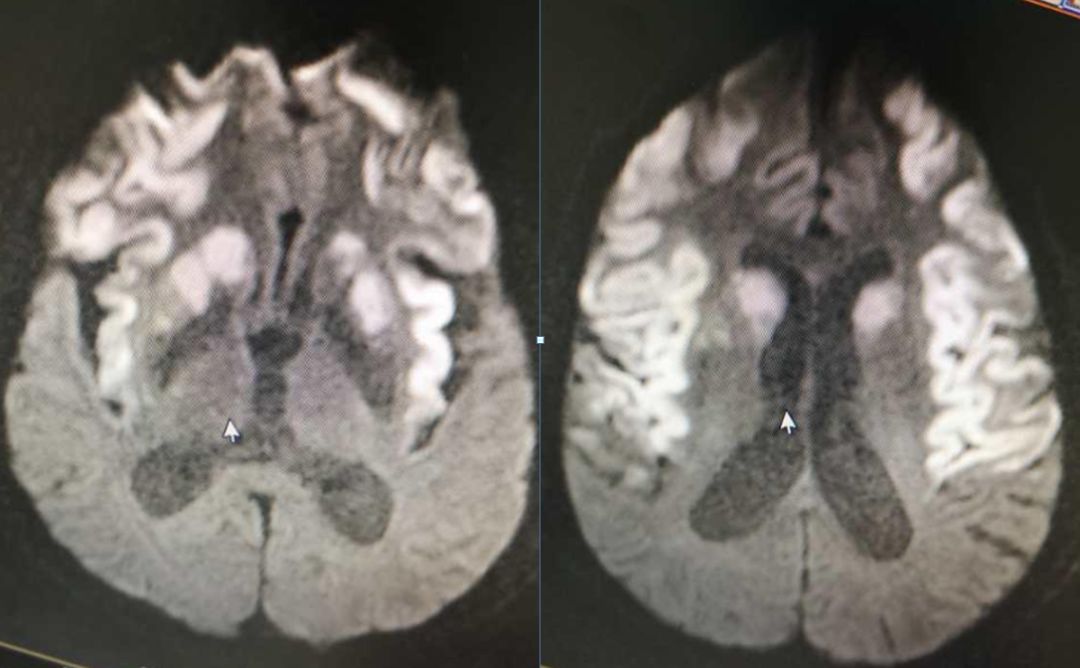

男,29岁,言语不清,协调不良以及行走不平衡3周。

答案:*洛因海**海绵状白质脑病。*洛因海**海绵状白质脑病(heroin spongiform leukoencephalopathy,HSLE)是因烫吸或静脉注射*洛因海**而引起的中枢神经系统器质性疾病。临床和影像特点如下:

4. CT和MRI影像显示病灶位于脑白质区,呈广泛、对侧性损害(小脑半球、脑干、内囊后肢、胼胝体压部及大脑半球后2/3),其中小脑受累严重,小脑中线两旁、边界清楚的对侧性类圆形或蝴蝶样病灶最具特点(蝶翼征);在脑干部位,若同时有红核及网状结构受累,则可见“蟹钳征”;在内囊后肢则呈“八字征”。病变在T1W为低信号,T2WI为高信号,FLAIR为高信号,且增强扫描一般无强化.5.病理显示脑白质空泡样变。